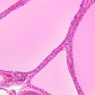

The thyroid gland (slide B-51, lead hematoxylin [10x, 20x, 40x, 40x]; B-52, H&E [10x-labeled, 20x, 40x-labeled, 40x]; B-53, PAS [2.5x, 10x, 20x, 40x]) consists of many closely packed, roughly spherical structures known as follicles, which are enclosed in a thick connective tissue capsule. Connective tissue septa extend from the capsule into the substance of the gland, carrying numerous blood vessels. Follicular cells are arranged as shells of simple cuboidal epithelium surrounding a gelatinous mass known as colloid. Look for a ring of epithelial cells around the homogeneous, pink-staining colloid. The cytoplasm of the follicular cells (principal cells) is faintly basophilic. The follicular cells secrete thyroglobulin, a glycoprotein, which is stored extracellularly in the colloid. In response to TSH, the follicular cells endocytose the colloid and hydrolyze it to form thyroxine. You can see where colloid has been resorbed because this process leaves small holes in the colloid adjacent to the follicular cells. These holes are known as resorption lacunae (B-52 [10x, 20x, 40xlabeled]). Very active follicles may exhibit a columnar epithelium and increased numbers of resorption lacunae. Between follicles, the stroma of the thyroid gland consists of a thin layer of connective tissue and a rich capillary network. Parafollicular cells (light cells or C cells) are located in the connective tissue between follicles or adjacent to follicular cells within follicles. When they lie within the follicular wall, the parafollicular cells do not reach the lumen. Parafollicular cells are slightly larger than the follicular cells and, in H & E preparations, have a more lightly stained cytoplasm (B-52, H&E [10x, 20x, 40x-labeled] [10x-labeled, 20x, 40x-labeled] [10x, 20x, 40x] [10x, 20x, 40x]; B-53, PAS [10x, 20x, 40x]). Parafollicular cells are readily identifiable in slide B-51 (stained with lead hematoxylin), where they appear as purplish-black structures in which the nuclei are difficult to discern (B-51 [10x, 20x, 40x-labeled]). These cells secrete calcitonin, which lowers serum calcium levels by inhibiting bone resorption and accelerating osteoid calcification.